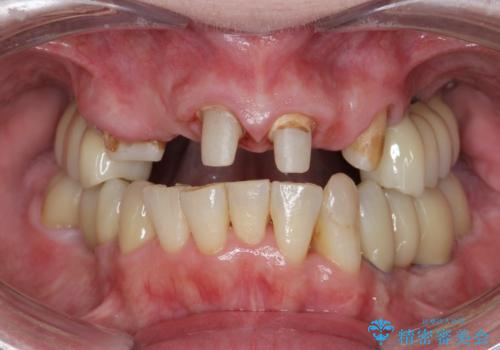

多発した虫歯による咬合崩壊 インプラントを用いた全顎治療

- 「これまで歯の治療をおざなりにしてしまい本当に後悔している。 時間と費用がかかってもいいので、しっかりと安心してかめるような状態にしてほしい。」、と全体的な治療を希望され来院されました。

歯の破折・再発した大きな虫歯・根尖病変・歯の欠損、これらの問題を根管治療・歯周外科・インプラント治療・セラミック補綴を行うことで一つづつ解決し安定した咬合状となるよう治療を進めます。